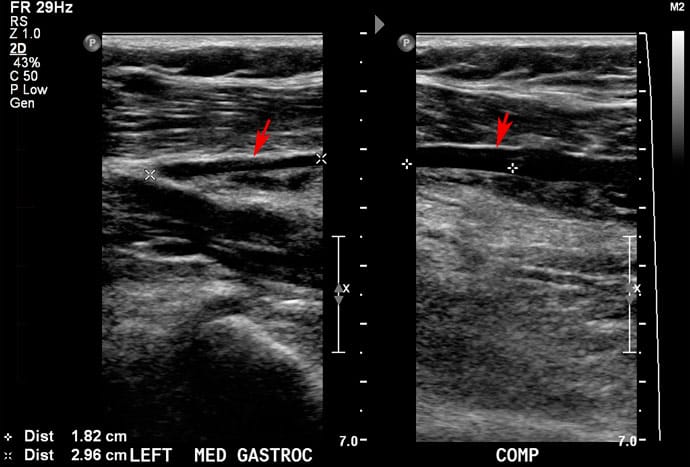

The diagnosis of DVT based on symptoms alone can be difficult. A venous doppler ultrasound is frequently ordered to confirm the diagnosis. Ultrasound machines use sound waves to detect blood flow in veins and arteries. A clot can be detected because of the decreased blood flow in the veins. Ultrasound is painless and does not have any major side effects. Sometimes blood tests are also used to help in the detection of blood clots.

Ultrasound evaluation demonstrates the presence of a blood clot (deep vein thrombosis) in the leg. On the left, the vein (arrow) is compressed with the ultrasound probe and would normally collapse, however remains patent. On the right, the pressure is released and the same vein (arrow) containing the clot is more obvious.

[*Image courtesy Melbourne Radiology Clinic]